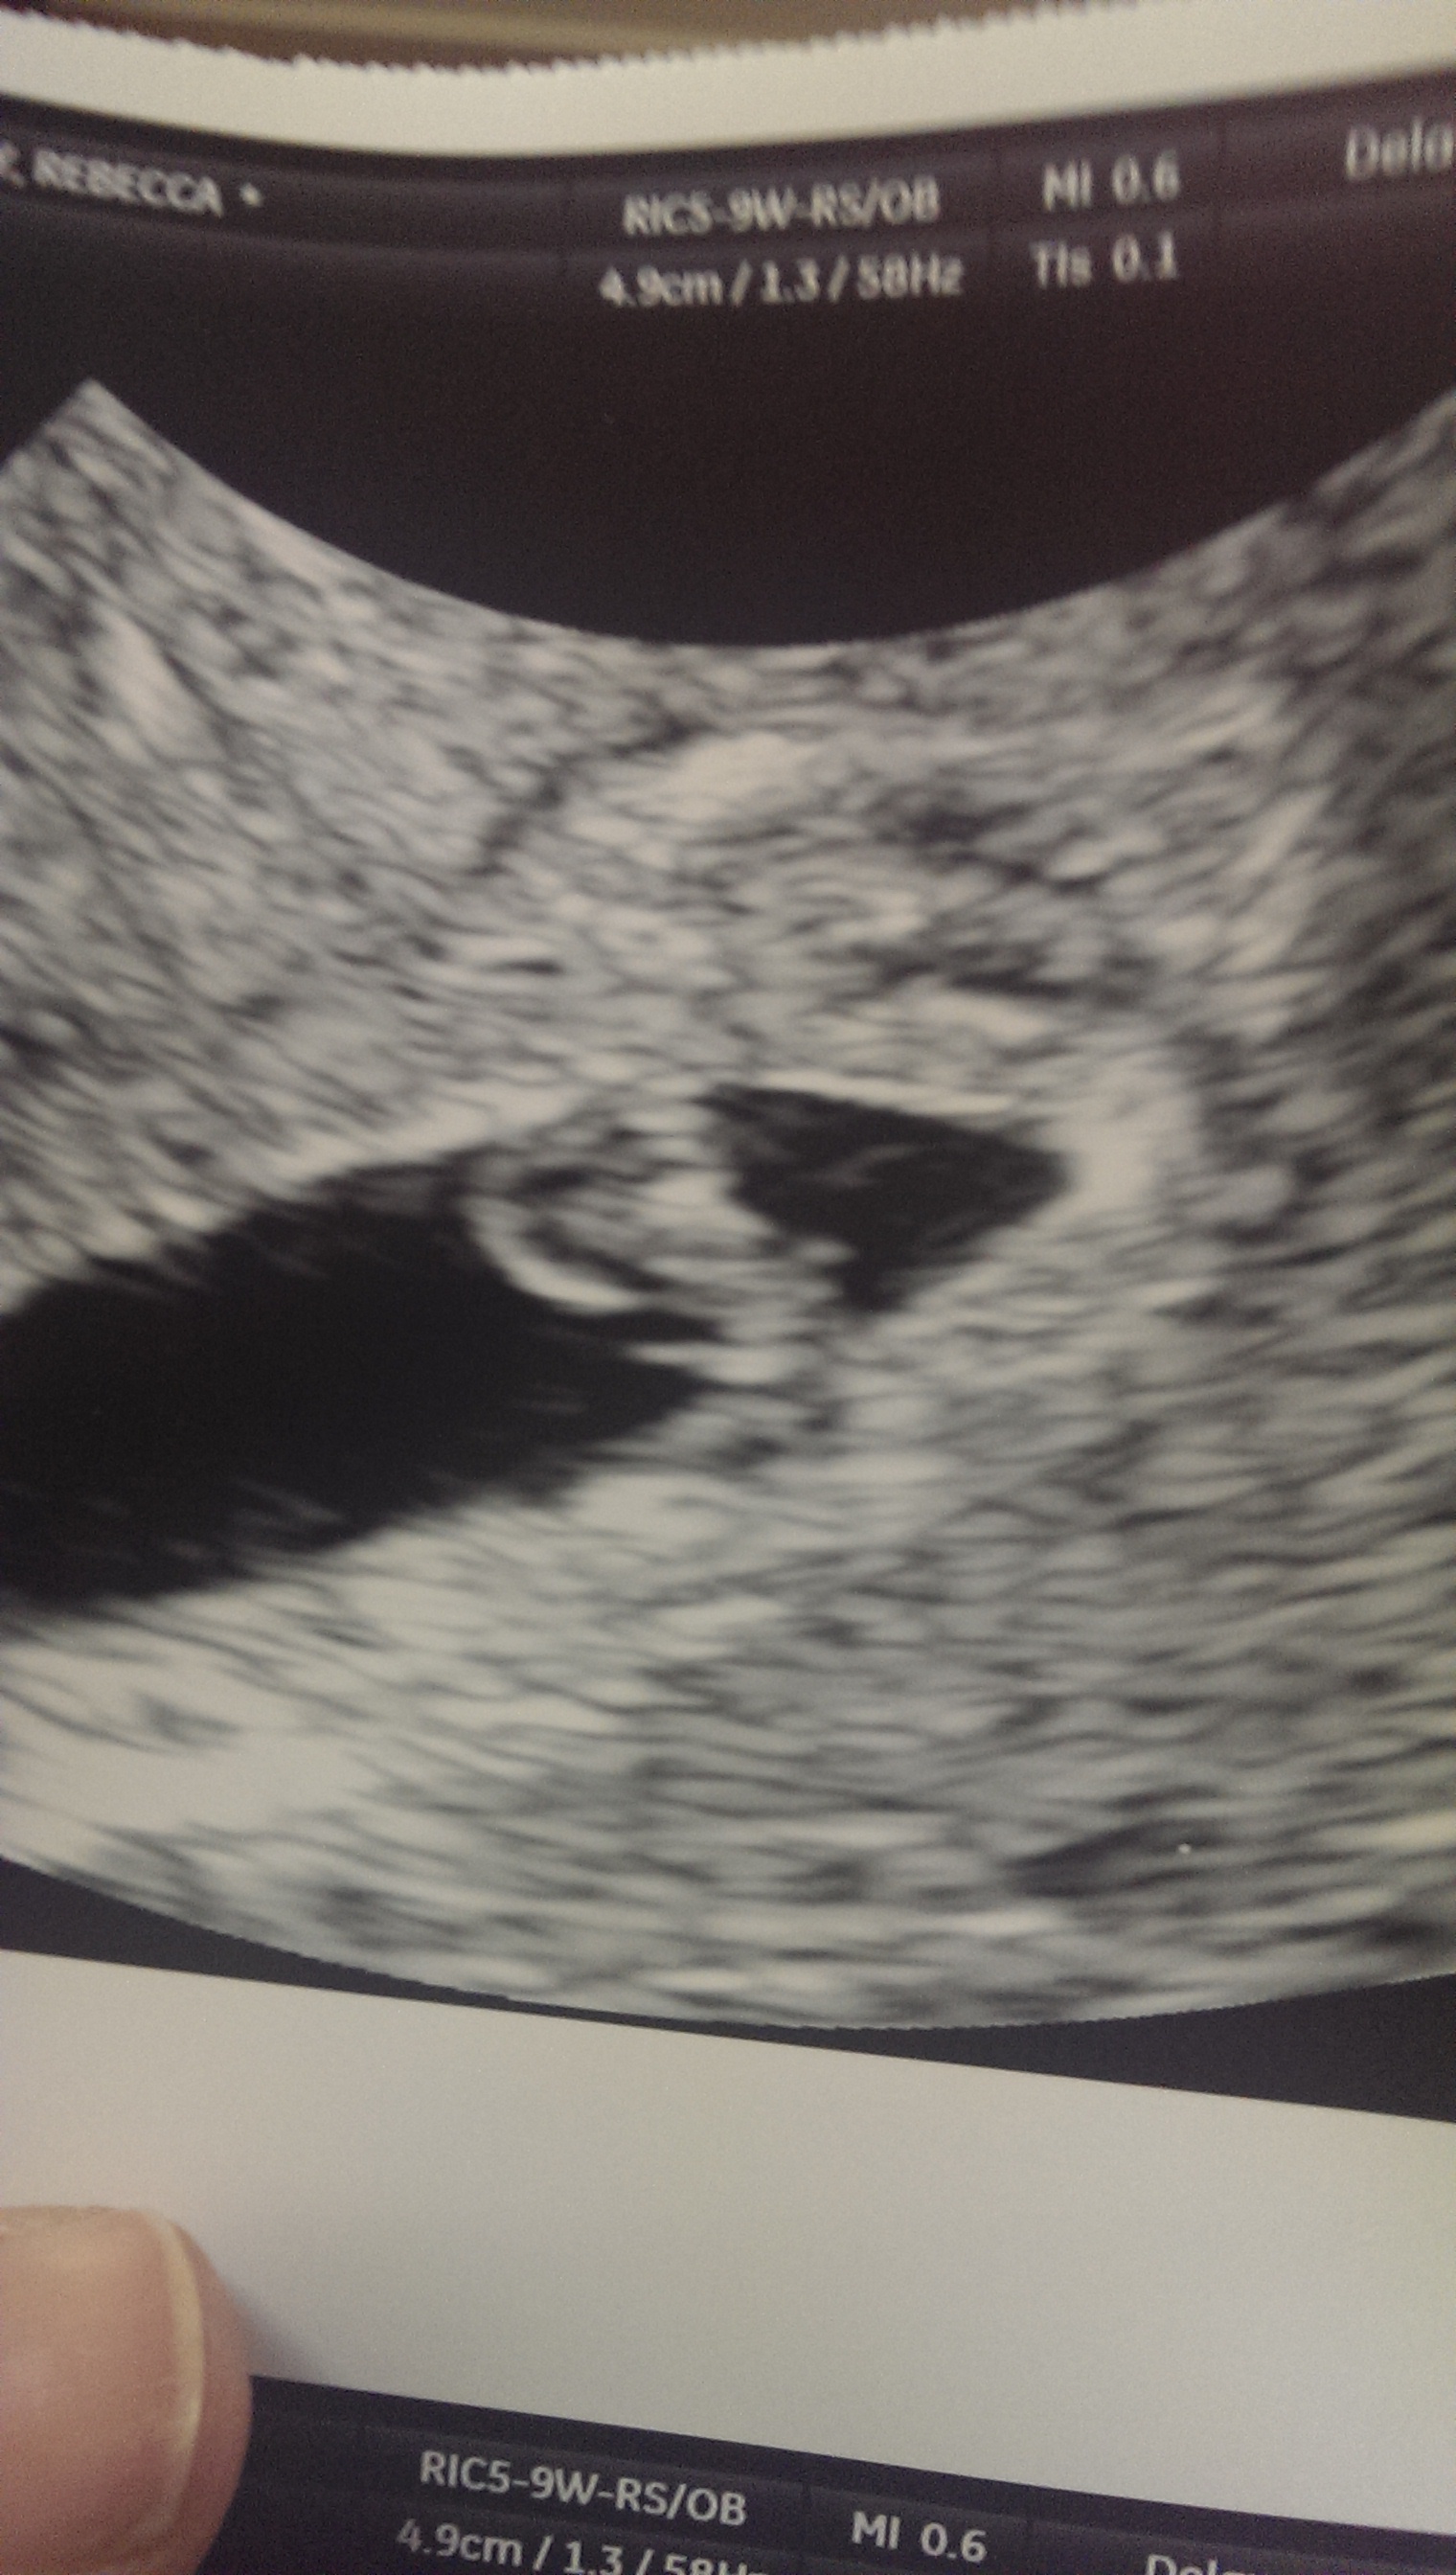

We are officially past our lost milestone! I went in for my second ultrasound this morning & we have one perfect little bean measuring 6w3d, with a heartbeat of 127bpm. I've never seen a heartbeat before, that was the most amazing thing. H & I both started crying immediately. The NP said by their dates, I should be 6w6d (I had 7w1d) & baby is measuring 6w3d, so things are right on track. My EDD is moved back 2 days to 9/16/13. I finally feel like I can let myself get excited about this one :)